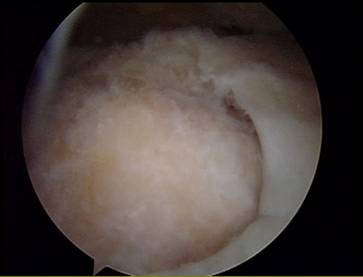

Schultergelenksspiegelung (Arthroskopie): intakter Sehnenansatz